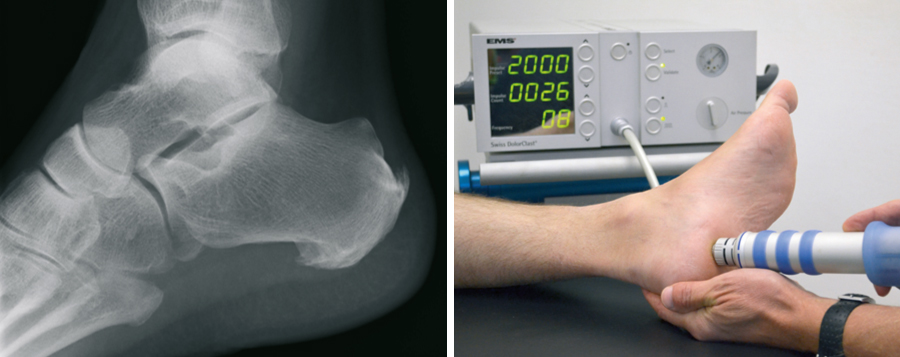

Calcaneal

The plantar Calcaneal (at the bottom of the heel) is caused by an overload of the longitudinal arch braced fascia. Connective tissue, excessive loads, malposition, but also overweight may be responsible. The congestion between the heel bone and the attachment site of this fascia is an increasing tissue damage associated with a ossification, called Calcaneal. Not the spur itself, but this tissue damage is causing the pain. They start appearing when putting pressure on it, but later also at rest. First of all the available treatments is the supply of special arch supports. Also injections directly to the Calcaneal, have their value. The shock wave therapy as proved to be very risk-free, which is carried out in our practice. Alternatively, X-ray irradiation effect healing.

Failure of all non-operating activities is also a surgical treatment option. Via a small cut at the inner edge of the heel fascia is nicked, the voltage decreases and the tissue damage can heal.